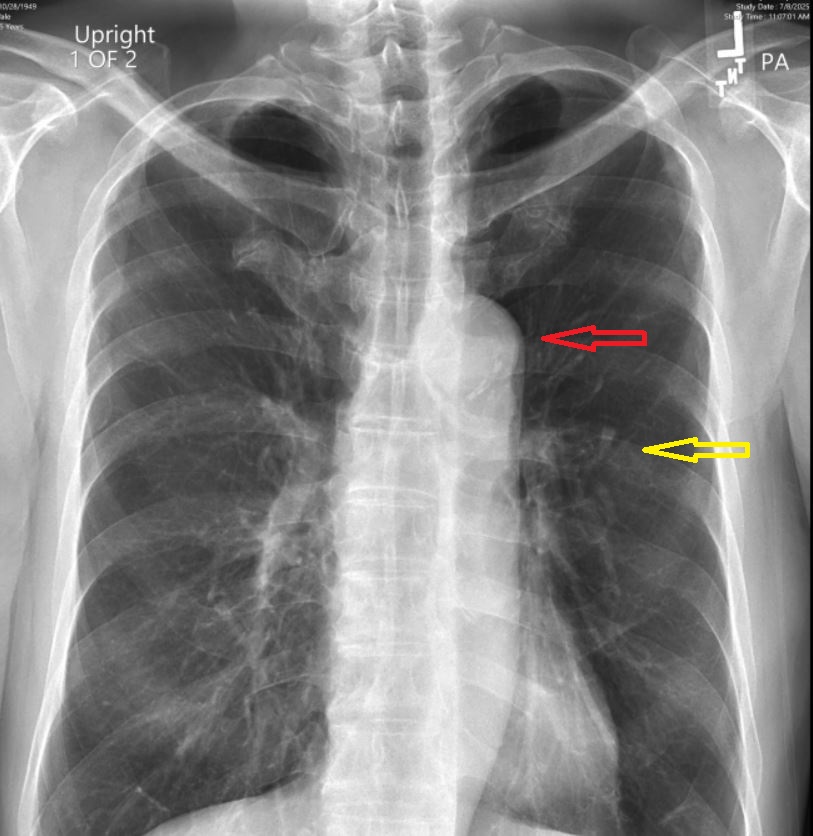

要来了透视光盘,前后左右共八张片子。自己看不懂,从一张片子上看,好像肋骨不是微小骨裂,简直就是骨折(下图黄箭头)。再仔细看,中间有个造影,越看越不像话,胸腔里怎么会有那么个玩意儿(下图红箭头)。上网查,那个玩意儿叫aortic arch,是心脏很大的动脉血管。人体里真是无奇不有。